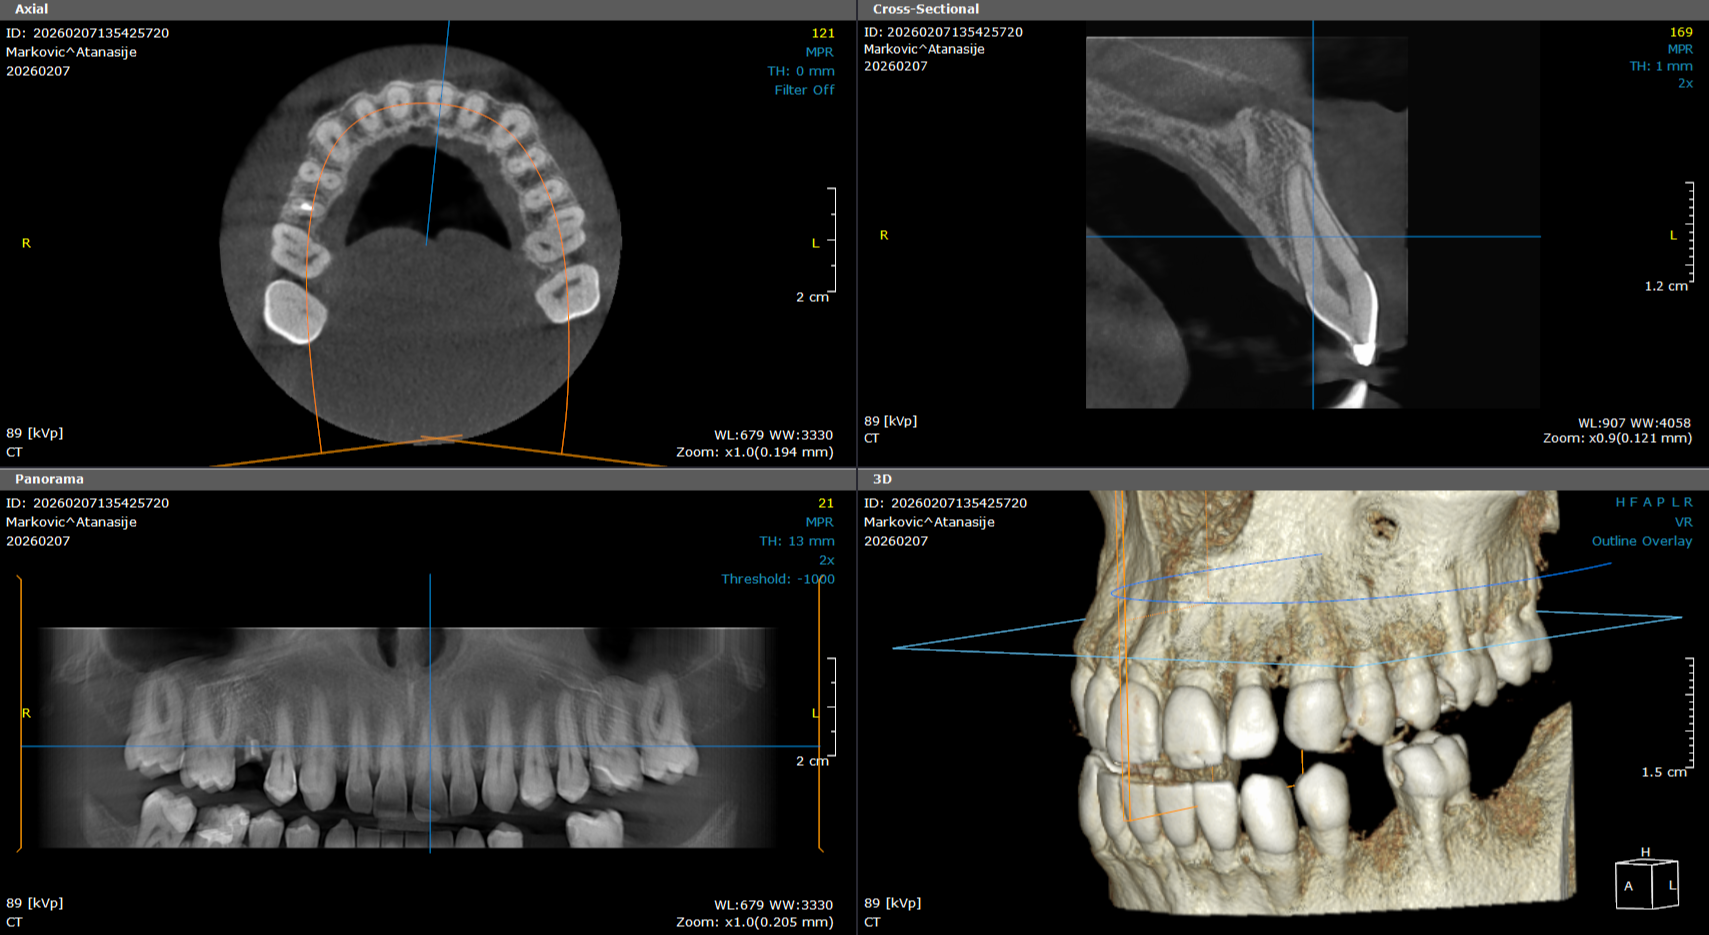

3d snimak - cbct obe vilice

3d snimak gornje i donje vilice je trenutno najkompletniji i najpouzdaniji snimak vilice, zuba i okolnih struktura. Koristi se u stomatološkoj dijagnostici za detaljan pregled, pri pravljenju plana za ugradnju implantata.

8 000,00 rsd